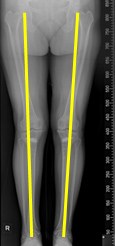

휜다리(O자형) 교정술

휜다리란?

- '안짱다리', 'O다리', 혹은 '오다리'로 불리는 휜다리는 다리를 모으고 바른 자세로 섰을 때 양 무릎이 서로 닿지 않고 떨어져 있는 상태를 말합니다.

- 뼈의 정렬 자체가 변형되어 일직선으로 향해야 하는 체중 부담선(고관절에서 무릎, 발목까지)이 무릎 안쪽으로 집중되어 있습니다.

- 주로 중년 여성에게서 많이 발견되는 증상입니다.

휜다리 교정술 (근위경골 절골술)

- 환자 다리의 변형 정도를 정확하게 파악하여 교정합니다.

- 무릎 안쪽에 가해지는 부하와 스트레스를 분산

- 최소절개를 통한 근육손상 감소로 빠른 회복 기대

- 자기 관절 보존으로 관절의 유연성과 운동성 향상

- 수술 이후 통증, 흉터, 입원 기간의 감소

O자형 휜다리를 방치할 경우

- O자형으로 휜다리를 방치할 경우 무릎 안쪽의 연골이 손상되어 걸음걸이가 망가질 수 있습니다.

- 관절염 증상이 있는 경우, 관절염 진행을 가속화하여 안쪽 무릎 통증이 심화될 수도 있습니다..

- 휜다리의 영향으로 족부, 고관절, 척추, 어깨 질환을 초래할 수도 있습니다.